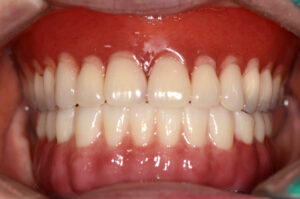

완료 후의 모습을 보시면 구강에 맞는 형태와

모양으로 임플란트가 완성된 모습을 볼 수 있는데요.

풀아치임플란트의 경우 보철물의

각도나 위치, 상하 교합 관계 등을

정확하게 맞추는 것이 중요해요.

보철물까지 완료된 후의 사진이에요.

.

위에 사용하시던 틀니와 교합이 알맞게

맞물리는 것을 볼 수 있는데요.

심미적으로도 만.족하시고 틀니처럼

탈락하지 않아 좋아하셨어요.